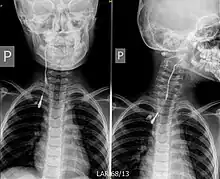

| Fistulogram (sinogram) of a right branchial cleft sinus. | |